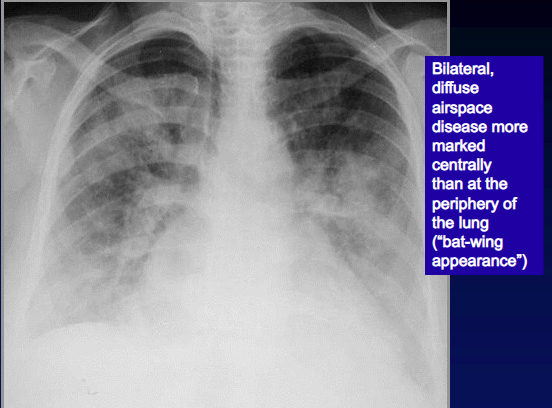

What’s your diagnosis?

ARDS